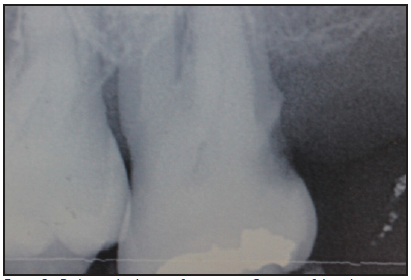

The incidence of root caries in the older adult has been estimated at approximately 1.6 root surfaces per 100 root surfaces at risk. The nature of the root caries appear to be more severe in males and most likely to affect the molar regions (Figure 1 and Figure 2). Significant factors associated with root caries include decreased salivary flow, impaired manual dexterity, and systemic conditions requiring medications that decrease salivary flow. Other risk factors influencing the higher incidence of root caries among the older patient include abrasion at the cementoenamel junction, fixed bridgework, removable partial dentures, long-term institutionalization, and soft diets consisting of refined sugars and sticky, fermentable carbohydrates. Root caries prevention and therapy include application of topical fluoride, dietary counseling, plaque control, and prevention of gingival recession.

Figure 2. Radiographic Image of root caries. Courtesy of dentalcare.com

Figure 2